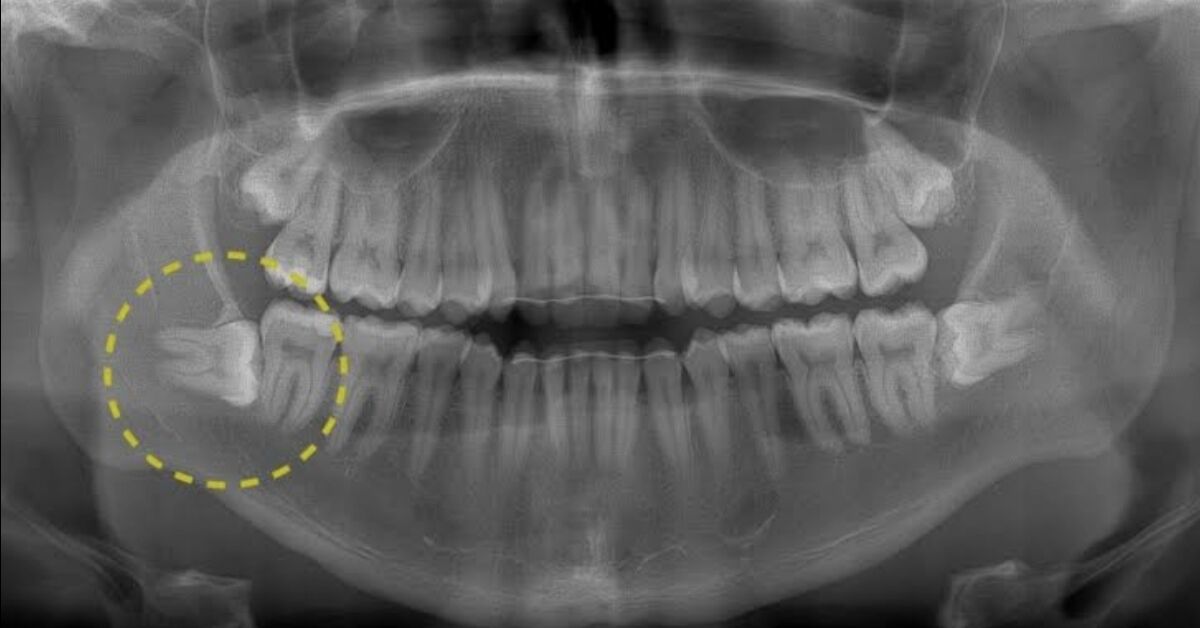

Зубы Мудрости Симптомы Фото

Зубы Мудрости Симптомы Фото 111 фотографий